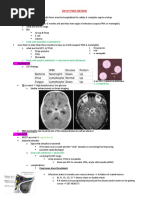

PEDIATRIC INFECTIOUS DISEASES

DISORDER EPI PATHO CLINICAL DIAGNOSIS TREATMENT

Atypical 1 5 yodueto mycobacteria unilateral firm tetracyclines

fluoroquinolones

mycobacterial puttingthings futteratehbadillus painlessprogressive copy macrolides

disease in mouth Lap anterior

cervicalorsubmand

sulfonamides

for 4 6weeks

mono kissing Epstein Barr classic triad Meteorite'Ab

EBV feverLAD

pharyngitis Atypicallymphocytes Supportive

disease mononucleosis screen

splenomegaly wenlargednuclei

humansare cheek

Erythema parvovirus Slapped

rashonface

infectiosum onlyhost Big Clinical supportive

lacyreticularon inflammatories

bodyhandsfeet

Hand-foot- soresinmouth

children logo Coxsackie

virus clinical

and-mouth Suappertive

disease typeA II 8119Wh inflammatories

Herpes HSV HSV HHV3 HHV4 HHV5 HHV6 HHV HAVE

orallesions genitals varicella EBV CMV roseola Kaposi's

simplex encephalitis

neonatal and herpesmonohepatitis otitis

media sarcoma

yegg meningitis

lymphoma

Zoster

Fetinitis wfever

encephalitis pneumonia encephalitis

notacute

riskfactorsfor orthomyxovirusfevercoryza rapidantigen if Sx48h15

Influenza comp 6540 strainsA B c coughmalaise goldstandard tamifuoseltamivir

immunocomp headache culture inhaledrelenza

isper

pregnant

comp AOM Paramyxoviruscoughcoryza ftp il9teyal.diffuseczanamivir

supportive t

A

Measles pneumonia

diarrhea

transmittedvia conjunctivitis serologic

confirmation

vitamin

respdroplets Koplikspots

mmrvaccine

uninitiated pitamigginsteightemYaieshistainsicaface Dmtryth

self limiting

Mumps childbetween transmittedvia anorexia parotitislabs leucopenia supportive

2 940 respdroplets comp orchitis lymphocytosis Mccauseof

aseptic meningitis amylase pancreatitis

Bittiageat colds needing nasopharyngealmacrolideaby

Pertussis considerinadults ram inspiratorywhoopswab culture azithromycin

wcough zwks bacteria residualcough orTMPSMX

goodaycough ramylase

Pinworms Children

3

enterobiasis

vermicularis

depositeggsin

analitching tapetest

worseatnight

fever

canseeeggs

onmicroscopy

albendazole

or

Mebendazole

Roseola

6monthsto HHVband recover rash

2yearsold spreadsfrom clinical supportive

rubella

tiffin.fi nimbsifcongenital s

maculopapular w

supportive

Rubella syndromes

congenital

cephalocaudalspread

serologicEla

data's van.ie sieniitigisiietrigitttateat mm

clusterofvesicles symptomatic

Varicella unvaccinated Zoster dewdropsonrose tzancksmear Iacyclovir

becomeslatentin petalinvarious multinucleated

rootganglion stages

dorsal giantcell